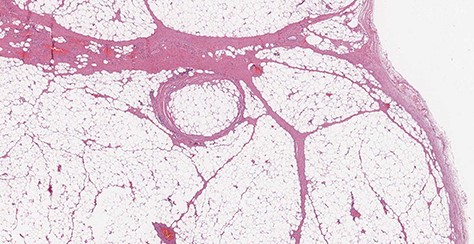

A 69-year-old woman was referred because of recurrent episodes of vomiting with concomitant regurgitation of a fleshy mass in the mouth and multiple episodes of asphyxia. The patient had a long history of heartburn and a GERD-HRQL score of 18. An upper GI endoscopy revealed a long pedunculated polypoid mass covered with normal squamous epithelium (Fig. 6). A computed tomography (CT) scan showed a fat-density mass in the esophageal lumen, originating about 1 cm below the upper esophageal sphincter and extending caudally in the esophageal lumen. A flexible endoscopic procedure was performed under general anesthesia and orotracheal intubation. An endoclip was placed at the base of the stalk in the cervical esophagus, and a snare resection of the pedunculated lipoma was successfully performed (Fig. 7). The procedure lasted 40 min. The patient began a soft diet on postoperative Day 1, which was well tolerated, and was discharged home on postoperative Day 2. Pathology confirmed a preponderant component of adipose tissue with a central fibrovascular core, covered by normal esophageal squamous mucosa (Fig. 8). At the 3 month follow-up visit the patient was asymptomatic, with a GERD-HRQL of 5 under treatment with proton-pump inhibitors.

Microscopic transverse section of the pedunculated lipoma composed by mature adipocytes, interspersed by blood vessels, surrounding a central fibrovascular axis; Tumor covered by intact esophageal squamous mucosa. No spindle cells are present. (H&E stain, ×4).